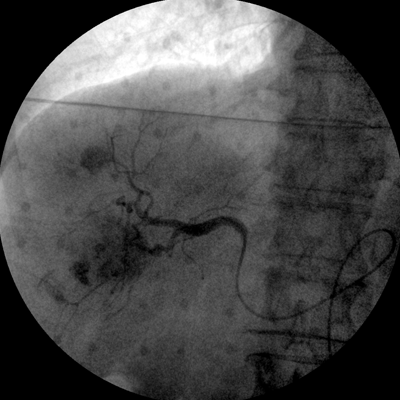

四維電動(dòng)運(yùn)動(dòng)控制,平滑定位,使得復(fù)雜角度快速實(shí)現(xiàn)。

專業(yè)的圖像處理系統(tǒng),為您提供高分辨率、高灰階圖像。